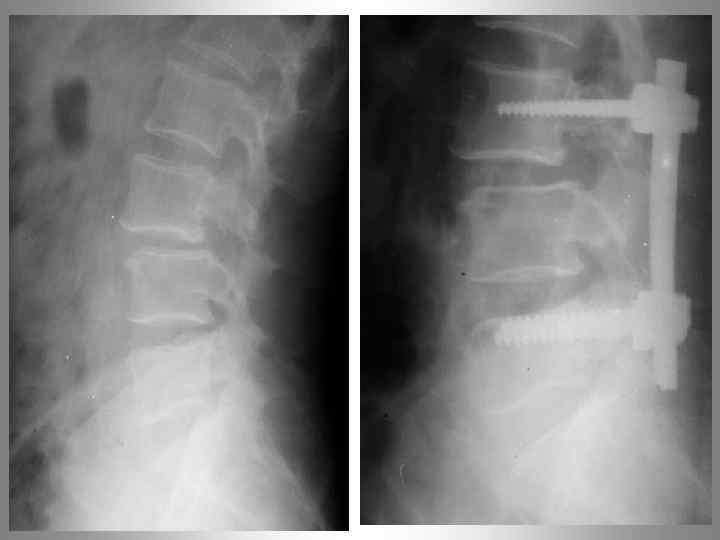

Операция Юмашева - Фурмана

Синдром смежного уровня Развитие патологических изменений в позвоночном сегменте, смежном с уровнем фиксации получило обозначение: “Cиндром смежного уровня”

Синдром смежного уровня 2004 2005 2006 Применение жесткой стабилизации одного или нескольких позвоночных сегментов приводит к серьезным изменениям в биомеханике позвоночника и перераспределению нагрузок